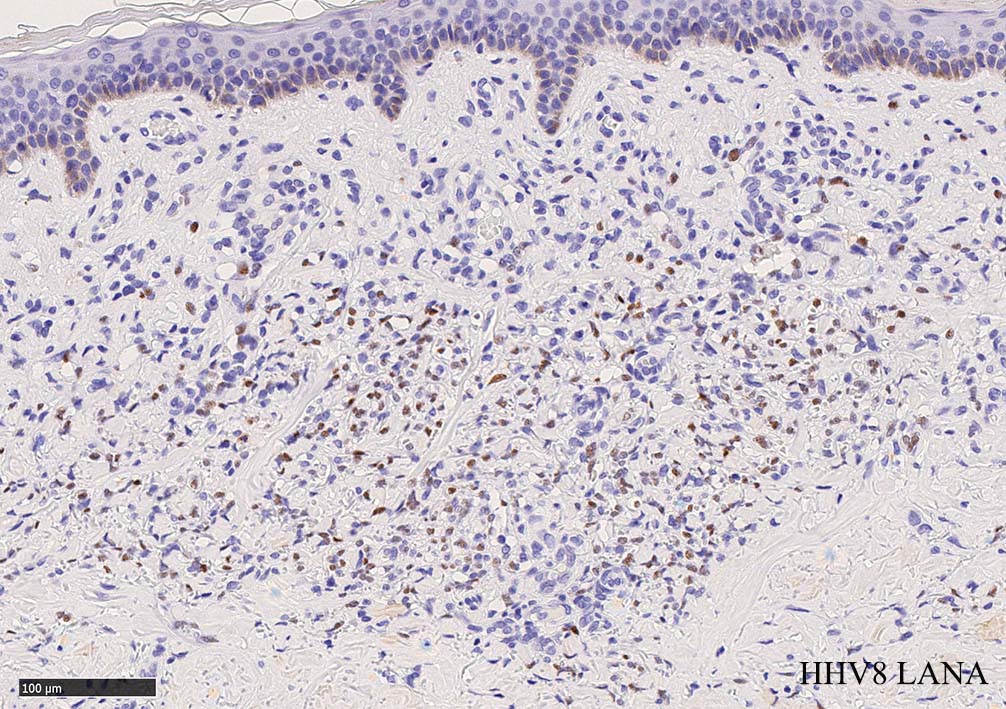

免疫染色, 分子病理学的検査

増生細胞はCD31, CD34, Factor Ⅷ, D2-40などが陽性を示す.

HHV-8の潜伏期関連抗原(HHV-8 Latency-associated nuclear antigen: HHV-8 LANA)が市販されており, 核が点状に染色される陽性所見がKaposi肉腫の確定診断に必須となっている.

組織からのPCRによるHHV-8の検出も診断に有用である.